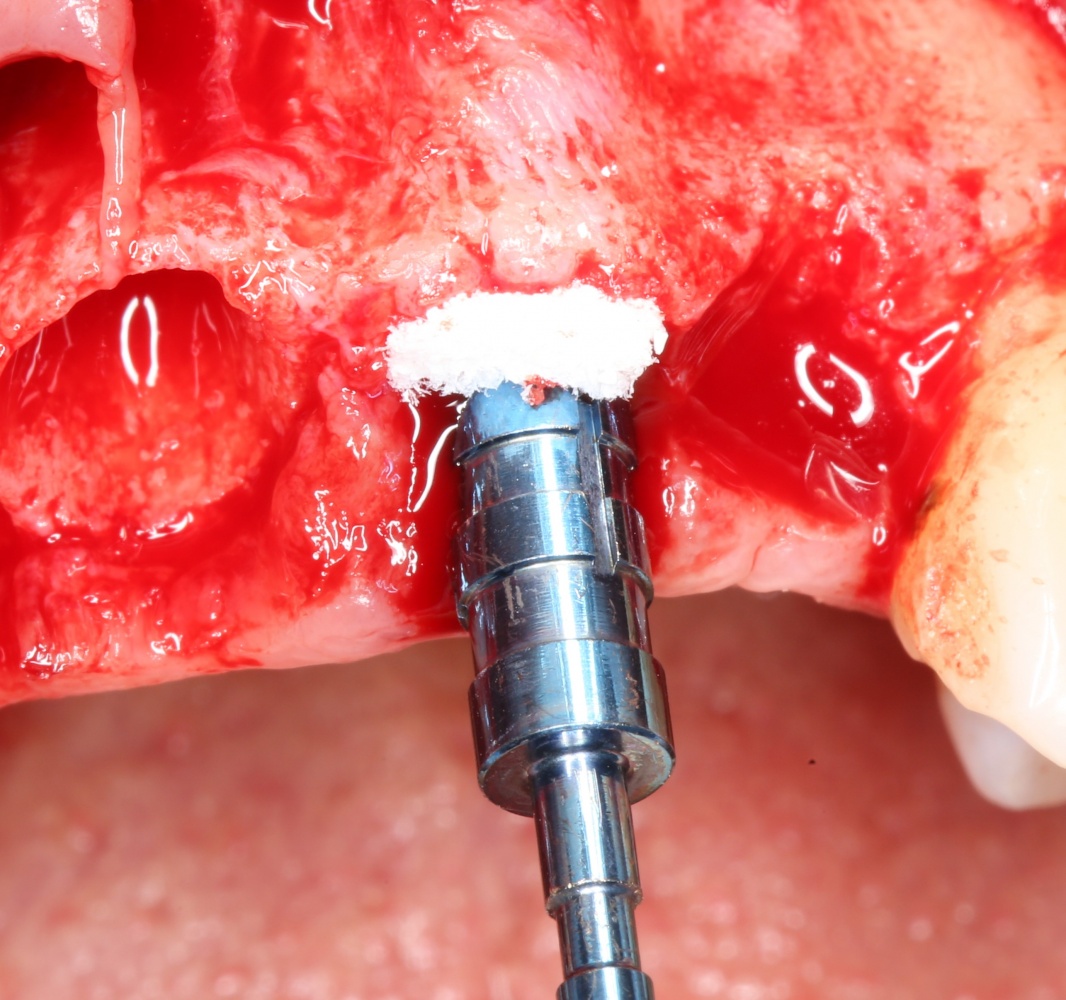

Графт адаптируется (с помощью скальпеля), устанавливается в нужное положение. Для этого, опять же, очень удобно использовать аналоги имплантов из имплантологического набора (в крайнем случае, остеотомы или пины параллельности):

Напомню, нет необходимости заполнять графтом всю лунку. Тем более — полость удаленной кисты или гранулемы. Поэтому 100 мг вполне хватает, чтобы аугментировать лунку любого объема.

Благодаря своим свойствам. Bio-Oss Collagen не забивается в подготовленную лунку импланта, не съезжает и не сползает при его установке: